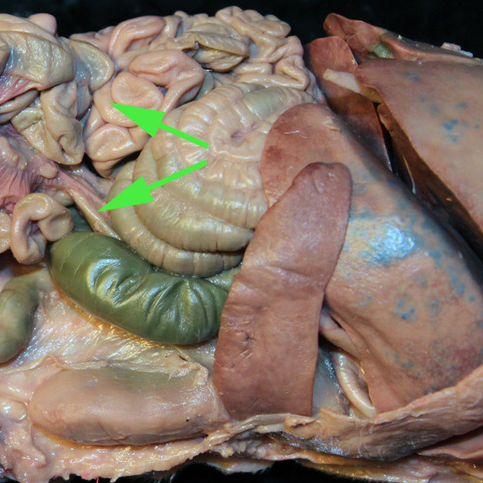

Areas of diffuse lymphatic tissue are found in the walls of the structures marked by the green arrows. They are called the///small intestine